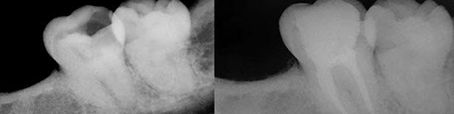

• Operatoria

La Operatoria Dental es la disciplina que tiene por objetivo diagnosticar y restaurar lesiones, alteraciones o defectos que puede sufrir un diente, restituyendo su forma, color y función, en equilibrio con el resto de la cavidad bucal. Se encarga de restaurar las lesiones de caries que no involucran al tejido pulpar. Se busca realizar una odontología mínimamente invasiva conservando la mayor cantidad de diente sano. Este objetivo se puede lograr gracias a la utilización de técnicas y materiales de última generación.